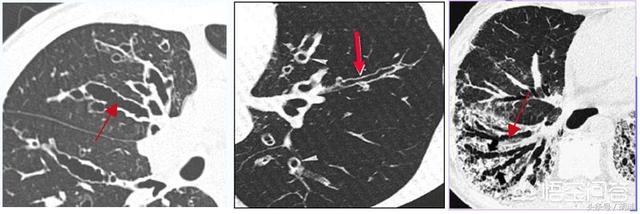

支气管扩张是一种气管结构破坏性疾病,大部分是继发性的,很多是其他疾病特别是感染性疾病的后遗症,有些则是间质性肺病之类的肺部疾病中气管受到被动牵拉导致。这个疾病本身不仅仅是支气管管腔的增大,更重要的是气管内部特别是气管壁上内衬的假复层纤毛柱状上皮的破坏,令支气管乃至周围肺策划完善的微环境受到损伤,失去对外界细菌的免疫功能,从而导致一系列症候群。下面和大家一起学习一下这个疾病。